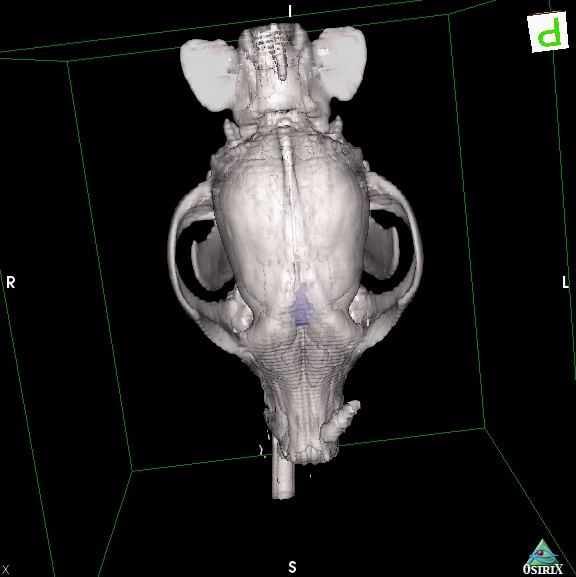

犬の脳腫瘍(髄膜腫)について

髄膜腫は脳の外側、頭蓋骨の裏側にある硬膜という膜から発生する腫瘍。つまり脳そのものから生じる腫瘍ではなく、脳の外側から発生して脳を外側から圧迫する。